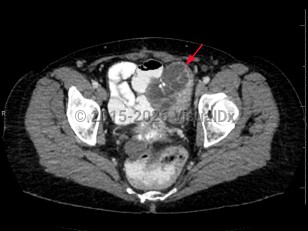

EndometriosisEndometriosis

Ovarian cancerOvarian cancer

Salpingitis

Pelvic inflammatory disease